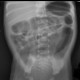

Bayi 3 hari dibawa bidan ke rumah sakit dengan keluhan perut kembung, menangis kencang, dan katanya belum mengeluarkan mekonium dari anusnya. Berdasarkan foto Xray abdomen di bawah. Apa diagnosis dan tindakan untuk bayi ini?

Berdasarkan foto rontgen abdomen dan klinis bayi 3 hari dengan perut kembung serta belum ada mekonium, diagnosis yang paling mungkin adalah Hirschsprung Disease (aganglionosis usus).

Gambaran rontgen: Terlihat pelebaran usus dengan air-fluid levels multipel, serta tidak tampak gas di rektum. Ini konsisten dengan obstruksi usus distal.

Klinis: Bayi baru lahir, perut kembung, dan belum BAB/meconium >48 jam sangat khas untuk Hirschsprung Disease.

Rontgen abdomen: Pelebaran usus, air-fluid levels, tidak ada gas di rektum